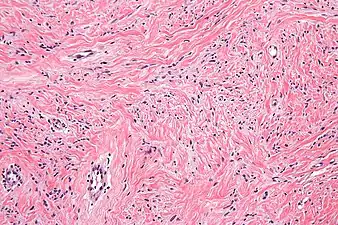

High mag. Mammary myofibroblastoma

Medical imaging may suggest but cannot prove that a tumor is MFB. Mammography, computed tomography scans, and magnetic resonance imaging of mammary[1][12] and extramammary[1][13] MFB typically show well-defined and well-circumscribed tumors which in almost all cases have no calcifications; these results suggest that the tumor is not malignant but do not indicate which type it might be. The diagnosis of MFB depends on the microscopic histopathology (i.e. appearances after proper tissue preparation and staining) of its pre-surgery biopsied issues. As shown in the upper image and the two images in the Additional images section seen below, both mammary and extramammary MFB tissues contain spindle cells, variable numbers of adipocytes (i.e. fat cells) and broad sheets or, less often, thick bundles of collagen fibers.[5] About 4% of cases have an epithelial tumor cell-like morphology,[5] i.e. the tissues are composed predominantly of epithelioid cells variably mixed with a minority (10% to 40%) of round, polygonal, and spindle-shaped cells.[19] Unlike malignant tumors, MFB tumors do not have: a) atypical cells except in the rare cases which contain small clumps of multinucleated cells; b) rapidly proliferating cells as defined by measuring the proliferative index (i.e. fraction of cells undergoing mitosis); or c) areas of necrosis (i.e. areas of dead or dying cells).[16] Microscopy of tumors in the spindle cell lipoma tentative variant of MFB show a mixture of mature fat cells, ropey collagen, and spindle cells in a myxoid (i.e. background connective tissue that stains blue or purple rather than the red of normal connective tissue) matrix.[18] The blood vessels in these tumors often appear hyalinized.[16] Tumor tissues in the tentative cellular angiofibroma variant of MFB contain spindle cells in all cases, fat cells in ~50& of cases, mast cells, peri-vascular infiltrates of lymphocytes, pleomorphic cells in some cases, and cells with some features of the malignant sarcoma cells in sarcoma tumors in rare cases. (The presence of these sarcoma-like cells does not seem to impact the prognosis of this variant.) All of these cells are in edematous-to-fibrous stromatous tissue.[16]